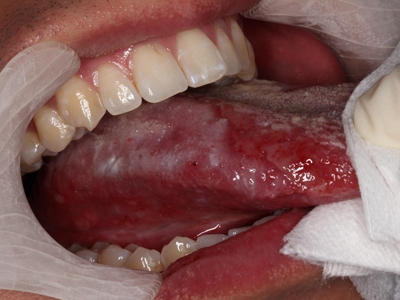

舌扁平苔藓一般认为发生率仅次于颊部扁平苔藓,好发于中年人,女性高于男性,且发病率随着年龄的增加而增加。病变多发生在舌前2/3区域,包括舌尖、舌缘和舌腹部。损害多样,一般较局限。

舌扁平苔藓的损害多样,舌背早期损害多为丘疹斑点状,灰白透蓝,开始时侵及丝状乳头顶部,而乳头下半部黏膜正常,以后整个乳头受累。由白色丘疹组成环网状损害,从中央逐渐向周围及深层扩展,并形成圆形或椭圆形灰白斑块损害,触之稍粗糙。舌乳头由萎缩逐渐光秃,向周围扩展,形成中央上皮萎缩变薄,呈鲜红或暗红平滑斑。在此基础上可发生糜烂,糜烂面愈合后,舌乳头恢复则非常缓慢。

舌背病损也可呈现乳头增殖角化和部分萎缩混合病损。病损可为孤立存在,也可呈不规则形状散在分布。舌腹部病损多呈网状、树枝状或线条纹,单侧或左右对称发生。

发生于舌尖及口底部的扁平苔藓较少见,可侵犯舌系带,并向前发展。舌侧缘、舌腹部扁平苔藓病损如为长期充血红斑,有斑点状增生突起、糜烂溃疡者,应注意观察或及时进行活体组织检查。